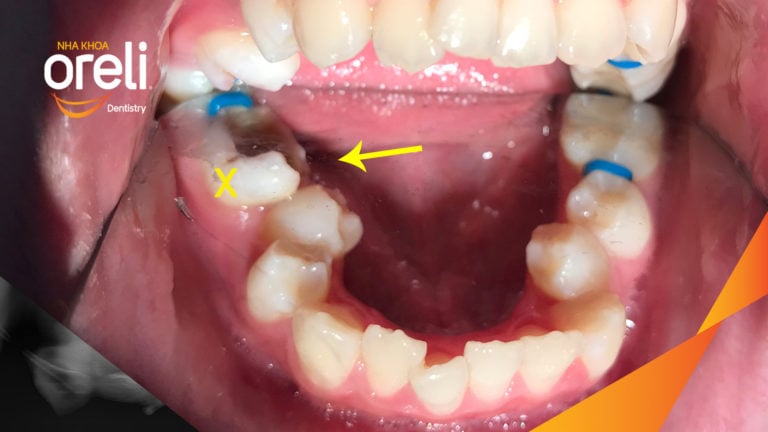

Ca niềng răng đặc biệt: kéo răng 7, 8 thay thế 3 răng 6 bị hư tại Oreli Niềng răngDi gần răng 7 8 Xem thêm